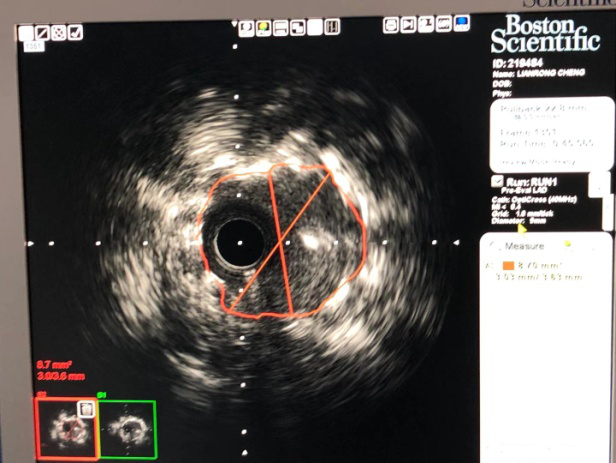

业务范围:常规开展冠状动脉造影术、左心及右心导管检查、食道及心内电生理检查、动态心电图、活动平板运动试验、动态血压监测、核素心肌灌注显像(ECT)检查、多排螺旋CT冠状动脉造影及三维重建术 、超声心动图等检查。熟练开展冠状动脉腔内成形术和支架植入术、冠状动脉内旋磨术、血管内超声(IVUS)指导下复杂冠脉介入治疗、临时及永久性心脏起搏器植入术;先心病房、室缺、卵圆孔未闭的封堵术。全年开展急诊急性心肌梗死介入治疗,每年抢救急性心肌梗死、急性冠脉综合征、急性心力衰竭、严重心律失常等高危患者3000余人。